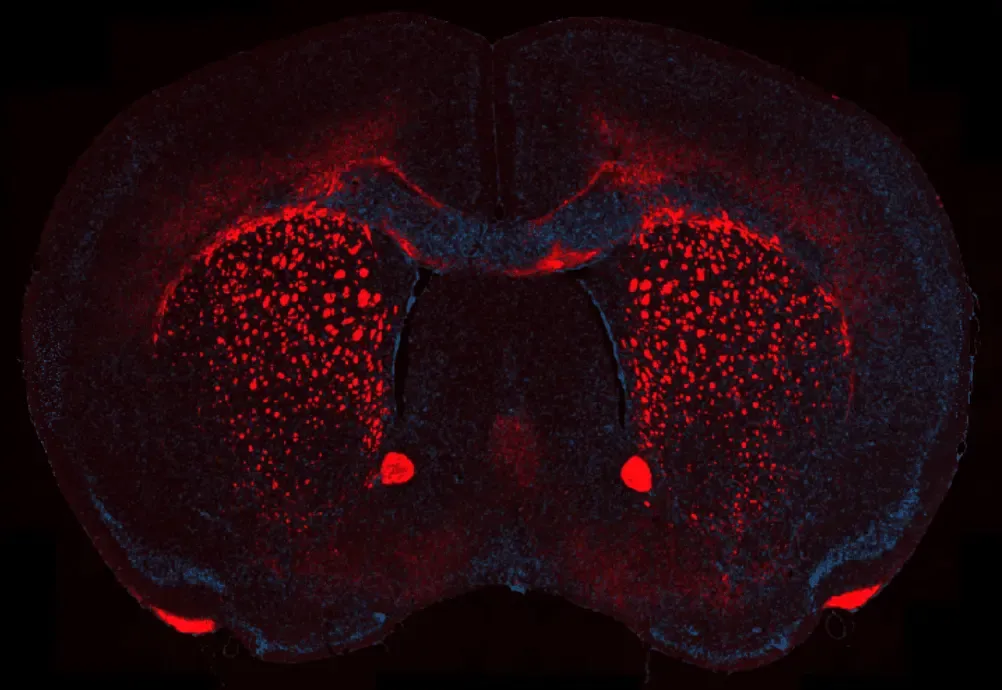

クプリゾン脱髄モデルにおけるミエリン喪失

クプリゾン誘発性脱髄マウス脳の冠状FFPE切片における代表的な脳梁領域 。ミエリン塩基性タンパク質 (MBP)は赤色で 可視化され 、 ミエリンの喪失および断片化領域を強調しています。一方、核 はDAPI (青色) で対比染色されています 。この染色法により、クプリゾン処理に伴う緻密なミエリンの特異的な減少が明瞭に示され、影響を受けた白質路全体における脱髄の重症度評価が可能となります。